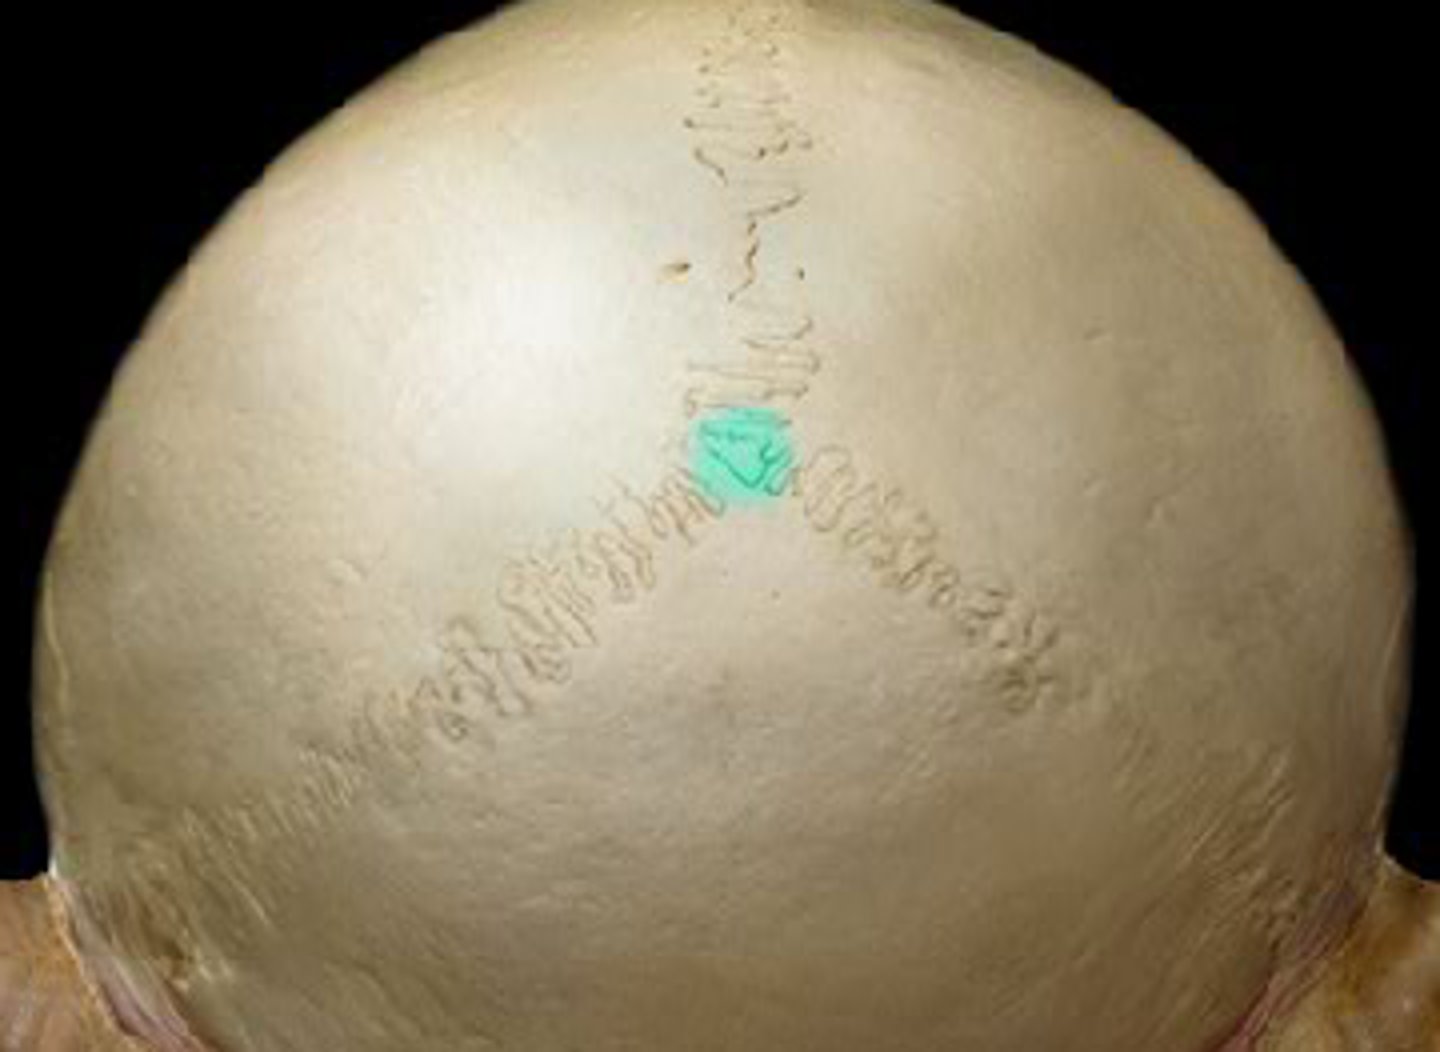

Bregma

junction of coronal and sagittal sutures

sagittal suture

between the two parietal bones

parietal foramen

parietal emissary vein passage

What are craniometric points (pterion, bregma, lambda) used for?

anatomical landmarks during surgeries

pterion

Junction of frontal, parietal, sphenoid, and temporal bones. Structural vulnerability as it is thin and middle meningeal artery is just deep, so hard head blow can result in subdural hematoma

the premature ossification of 1 or more sutures resulting in bulging at the fontanelle at the contralateral side. Treated by helmets and or surgery

Sagittal Craniosynostosis

premature closure of sagittal suture resulting in posterior elongation